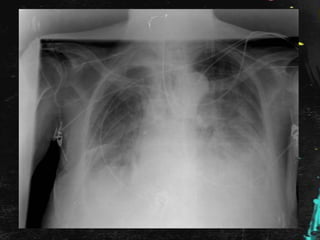

Rx de tórax en planta:

Se comenta el caso al Radiólogo, quien informa

que se trata de una falsa imagen

provocada por pelo largo recogido en moño

o coleta, por lo que es dada de alta con

seguimiento en consulta externa de Medicina

Interna con Rx de Tórax y analíticas; por la

presencia de imagen de vidrio deslustrado en

el TAC poco valorable por la escasa

inspiración de la paciente.

En este caso : Tenía pañuelo que ocultaba el

pelo duro, denso y espeso.

Al realizar la radiografía de tórax:

• Cuello en hiperextensión.

• Densidad del «moño»

Rx de tóraxen planta:

Se comenta elcaso al Radiólogo, quien informa que se trata de una falsa imagen provocada por pelo largo recogido en moño o coleta, por lo que es dada de alta con seguimiento en consulta externa de Medicina Interna con Rx de Tórax y analíticas; por la presencia de imagen de vidrio deslustrado en el TAC poco valorable por la escasa inspiración de la paciente.

Inmigrantes: • Cultura eIdioma. • Hábitos peculiares. • Enfermedades endémicas. En este caso : Tenía pañuelo que ocultaba el pelo duro, denso y espeso. Al realizar la radiografía de tórax: • Cuello en hiperextensión. • Densidad del «moño»